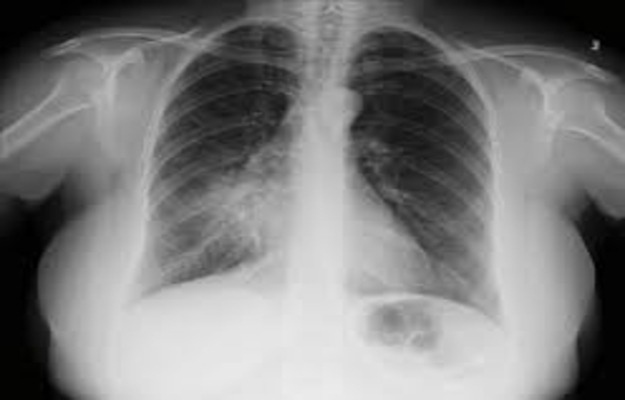

Quando o médico suspeita de atelectasia, a investigação começa com exames de imagem. O mais comum é a radiografia de tórax. Ela pode mostrar áreas do pulmão que parecem opacas, indicando a falta de ar.

Para um diagnóstico mais detalhado, a tomografia computadorizada (TC) de tórax é excelente. Ela oferece imagens mais nítidas e ajuda a identificar a causa exata do colapso, como um tumor ou um coágulo de muco.